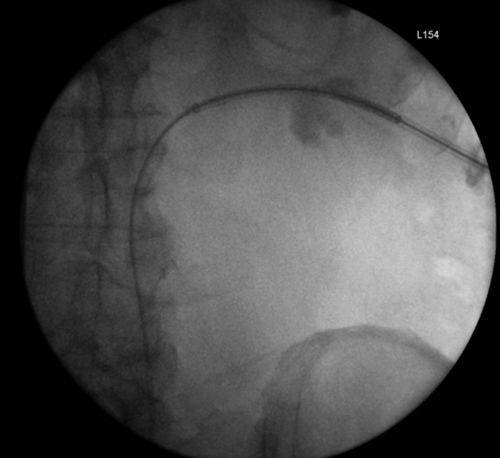

Figure 1: An example of the rendezvous procedure for an iatrogenic injury to

distal ureter during a laparoscopic pan-proctocolectomy for ulcerative colitis.